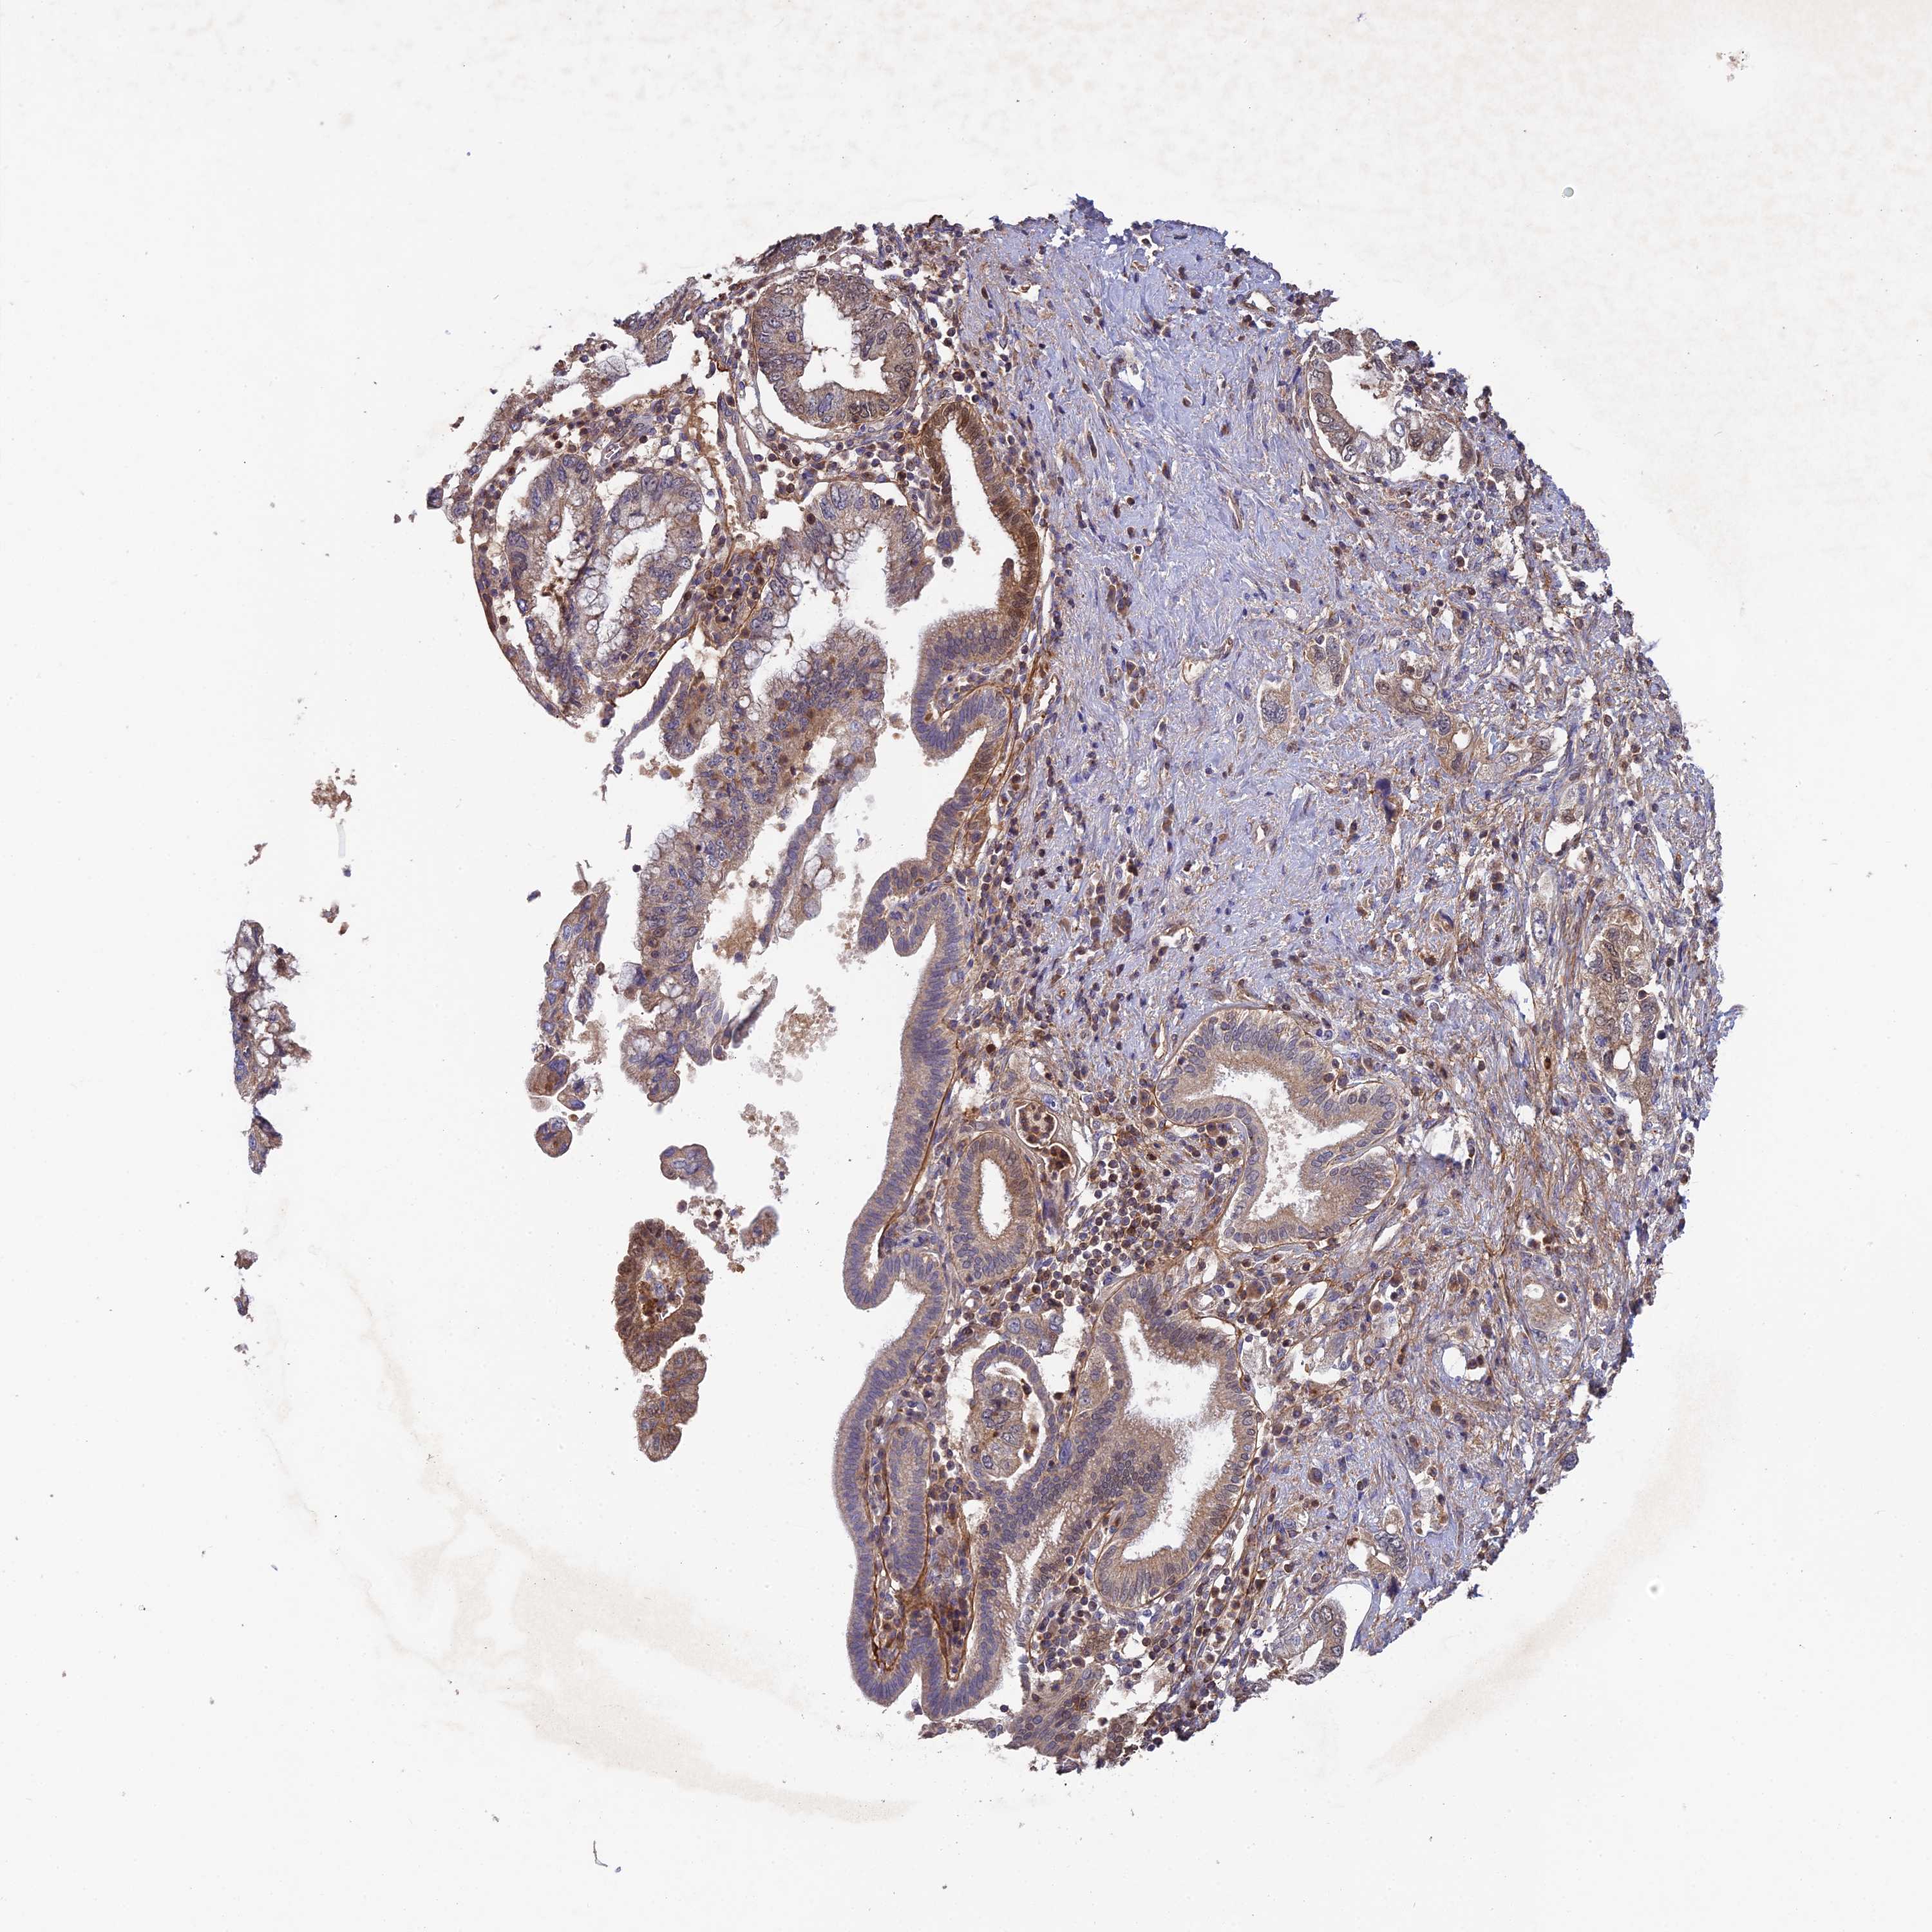

PANCREATIC CANCER - Protein expressioni

A mouse-over function shows sample information and annotation data. Click on an image to view it in a full screen mode. Samples can be filtered based on level of antibody staining by selecting one or several of the following categories: high, medium, low and not detected. The assay and annotation is described here.

Note that samples used for immunohistochemistry by the Human Protein Atlas do not correspond to samples in the TCGA dataset.

Antibody stainingi

Antibody staining in the annotated cell types in the current human tissue is reported as not detected, low, medium, or high, based on conventional immunohistochemistry profiling in selected tissues. This score is based on the combination of the staining intensity and fraction of stained cells.

Each image is clickable and will lead to virtual microscopy that enables deeper exploration of all samples and also displays staining intensity scores, fraction scores and subcellular localization as well as patient and tissue information for each sample.

Antibody HPA042620

Staining

High

Medium

Low

Not detected

Intensity

Strong

Moderate

Weak

Negative

Quantity

>75%

75%-25%

<25%

None

Location

Nuclear

Cytoplasmic/membranous

Cytoplasmic/membranous,nuclear

Adenocarcinoma, NOS